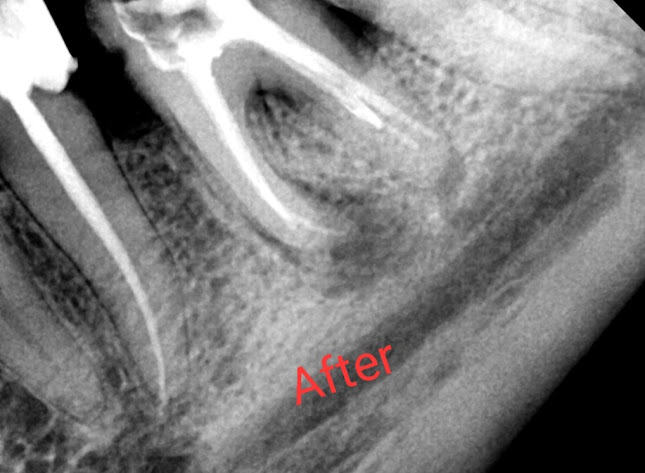

Рентгеново лъчение